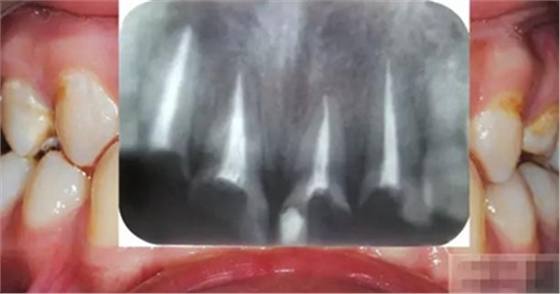

【檢查】12,11,21,22,均行玻璃離子充填,各牙不同程度部分充填物脫落,探(—),叩(—),冷刺激無反應(yīng),無松動(dòng),牙齦顏色粉紅,質(zhì)地堅(jiān)實(shí)而有彈性,點(diǎn)彩正常,牙結(jié)石(—);牙髓活力測試無反應(yīng)。

【診斷】12,11,21,22牙體缺損